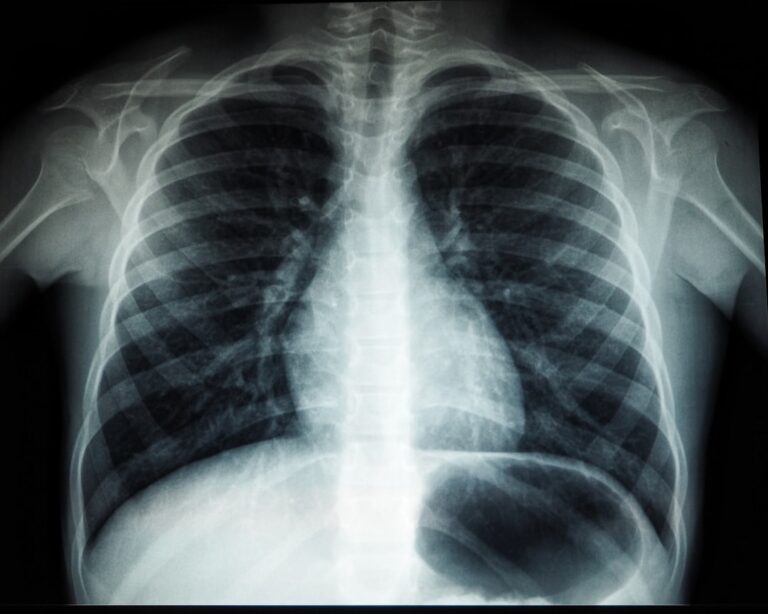

Sănătatea plămânilor este esențială pentru bunăstarea generală a organismului. Plămânii joacă un rol crucial în procesul de respirație, asigurând oxigenul...